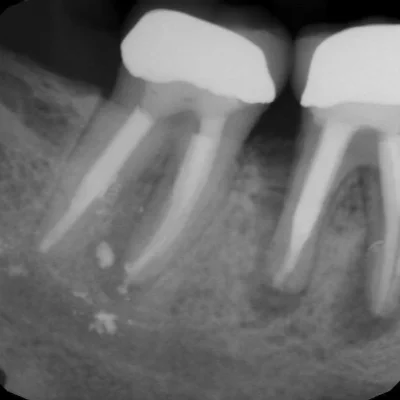

Dental X-Ray for Oral and Maxillofacial Evaluation

Dental X-rays are essential for diagnosing conditions that aren’t visible during a routine dental exam. At Alpha Imaging, we provide high-resolution dental radiography for

Tooth Decay Detection

Identifying cavities between teeth or under fillings.

Root Canal Planning

Visualizing root structure and surrounding bone.

Our dental X-ray system offers precise imaging with minimal radiation, making it safe for both adults and children. We work closely with dental professionals to ensure seamless integration of imaging into treatment plans.